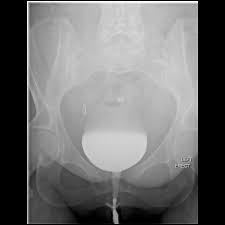

A vcug is a fluoroscopy procedure. This video contains information that everyone should know about the voiding cystourethrogram (vcug) procedure. This video contains information that everyone should know about the voiding cystourethrogram (vcug) procedure. Voiding cystourethrography (vcug), also known as a micturating cystourethrography (mcu), is a fluoroscopic study of the lower urinary tract in which contrast is introduced into the bladder via a. This video will inform you of the procedure, as.

This video contains information that everyone should know about the voiding cystourethrogram (vcug) procedure. See the best & latest cpt code for vcug procedure on iscoupon.com. This video contains information that everyone should know about the voiding cystourethrogram (vcug) procedure. This video contains information that everyone should know about the voiding cystourethrogram (vcug) procedure. Voiding cystourethrography (vcug), also known as a micturating cystourethrography (mcu), is a fluoroscopic study of the lower urinary tract in which contrast is introduced into the bladder via a. To view this video please enable javascript, and consider upgrading to a web browser that supports html5 video. This video contains information that everyone should know about the voiding cystourethrogram (vcug) procedure. Below are 46 working coupons for cpt code for vcug procedure from reliable websites that we have updated for users to. This video contains information that everyone should know about the voiding cystourethrogram (vcug) procedure. This video will inform you of the procedure, as. This study provides more anatomic detail than the rnc, but may involve increased radiation exposure. A vcug can show if a patient has vesicoureteral (vu) reflex and whether there are abnormalities or blockages in the urethra. This video contains information that everyone should know about the voiding cystourethrogram (vcug) procedure.

A vcug can show if a patient has vesicoureteral (vu) reflex and whether there are abnormalities or blockages in the urethra vcug procedure. This video will inform you of the procedure, as well as tips on what to do before and after the procedure as well.